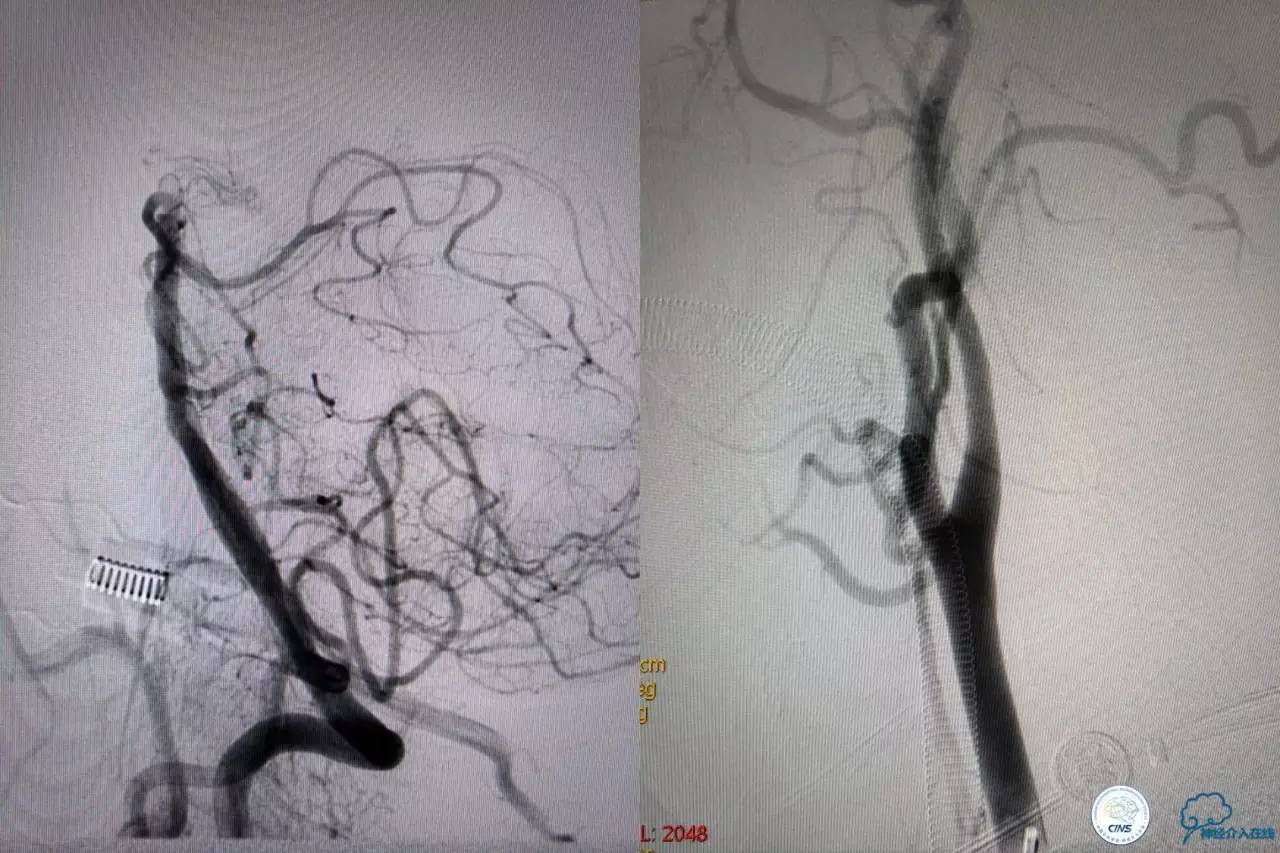

造影结果:右侧颈总动脉远端闭塞,前交通动脉开放,代偿方式:左侧颈内动脉→左侧大脑前动脉A1→前交通动脉→右侧大脑前动脉A1(反向)→右侧大脑中动脉供血区代偿。双侧大脑后动脉、右侧小脑上动脉及基底动脉顶端未见显影。

结合病史,体征及影像学,斟酌患者本次发病为基底动脉尖急性闭塞,发病机制:栓塞?右侧颈总动脉慢性闭塞?非责任血管,且代偿良好,暂时不需处理!

6F导引导管到位至RV2远端,rebar-18微导管及transand微导丝至右侧大脑后动脉P1远端。

solitaireAB4-20mm支架取栓。